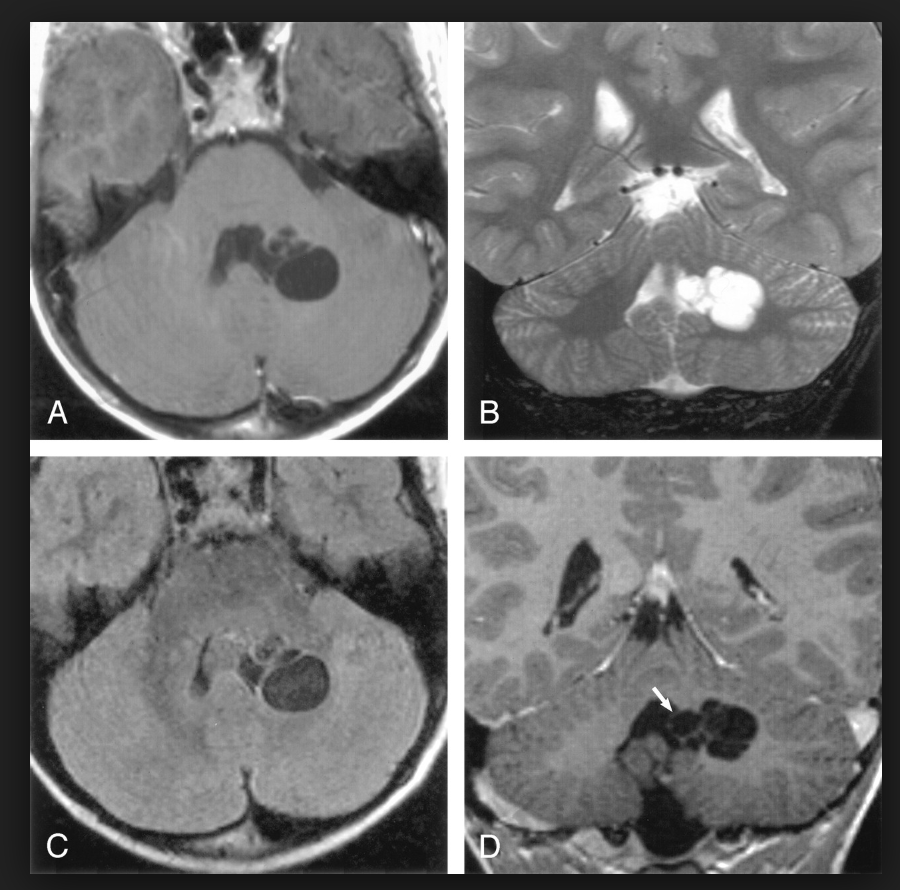

图3

图3 扩大的血管周围间隙